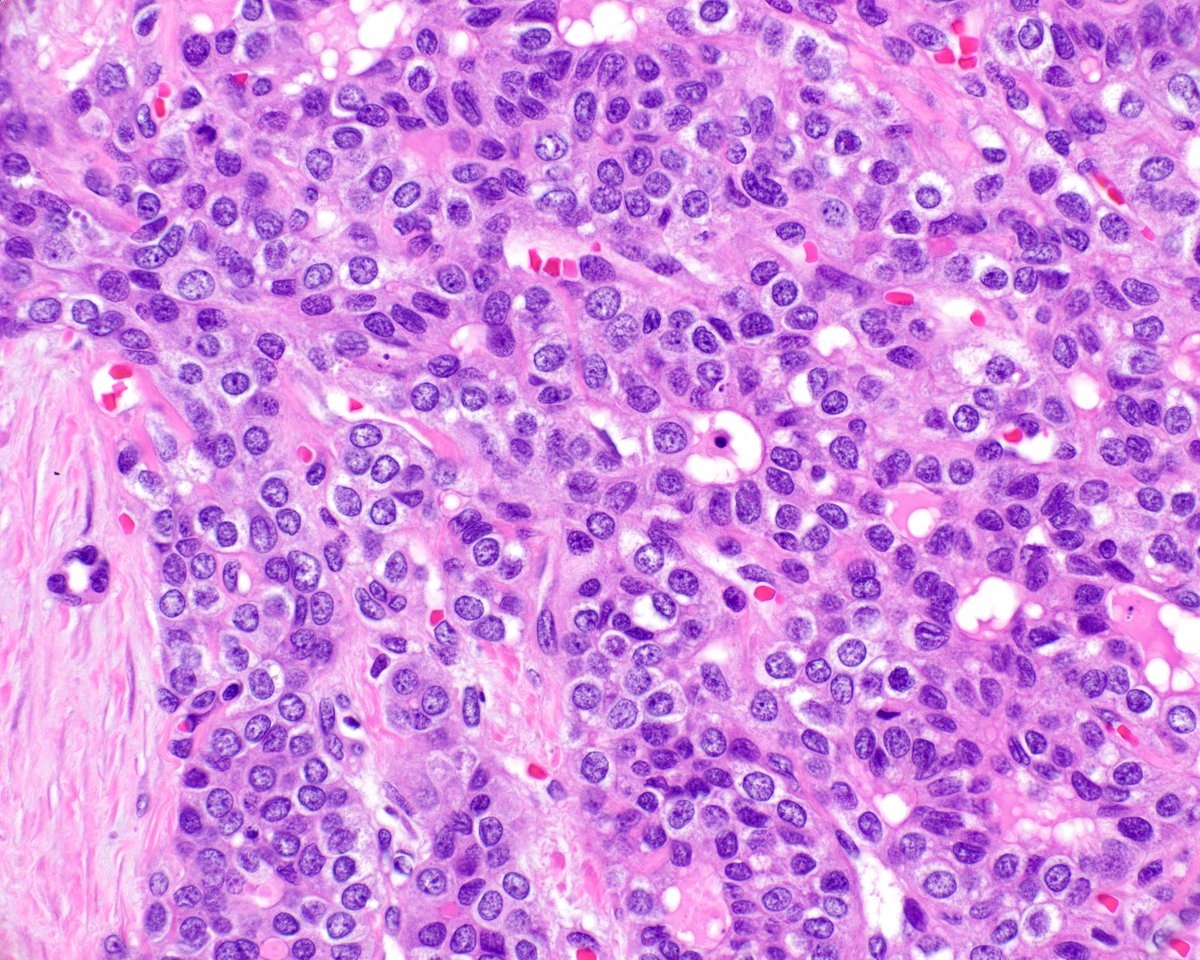

Granular/oncocytic lung carcinomas: what these are, and how they can cause diagnostic problems.

1/ Just out in @ModernPathology New study from our group: A distinct variant of aggressive lung carcinoma with peculiar pathologic features. We called these tumors “SAGA” (solid and granular adenocarcinoma) .. sorting them out was in fact a long and winding saga that led to some unexpected insights. 👇 modernpathology.org/article/S0893-… pubmed.ncbi.nlm.nih.gov/41580239/